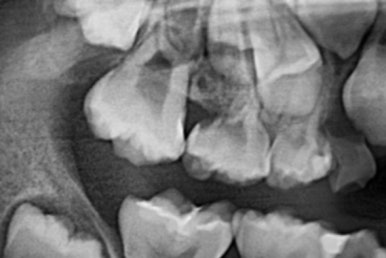

부산어린이치아교정 키다리아저씨치과에 처음 내원하셨을 당시의 X-ray 사진입니다.

이 때는 7세 3개월 때였습니다.

이번 환자분은 제 나이보다는 치아나이가 어린편이어서 다른 부위의 어금니도 나오지 않았긴 하지만 치과 검진에서 우연히 해당부위(화살표)의 치아가 문제가 있음을 발견하셨던 경우입니다.

이 X-ray는 다른 어린이의 사진인데, 위와 같은 경우를 방치했을 때 유치가 제 시기보다 조기에 빠지게 되고 그러면 어금니가 앞쪽으로 쏠려서 나고, 해당 부위의 영구치가 나올 자리를 아예 없애버립니다. 문제가 복잡해 지지요.